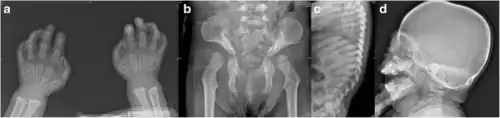

Mucolipidosis II (ML II) is a particularly severe form of ML that has a significant resemblance to another mucopolysaccharidosis called Hurler syndrome. Generally only laboratory testing can distinguish the two as the presentation is so similar, with high plasma concentrations of lysosomal enzymes, often fatal in childhood.[4] Typically, by the age of 6 months, failure to thrive and developmental delays are obvious signs of this disorder. Some physical signs, such as abnormal skeletal development, coarse facial features (e.g. bulging scaphocephalic head, flat nose), and restricted joint movement, may be present at birth. Children with ML II usually have enlargement of certain organs, such as the liver (hepatomegaly) or spleen (splenomegaly), and sometimes even the heart valves. Affected children often have stiff claw-shaped hands and fail to grow and develop in the first months of life. Delays in the development of their motor skills are usually more pronounced than delays in their cognitive (mental processing) skills. Children with ML II eventually develop a clouding on the cornea of their eyes and, because of their lack of growth, develop short-trunk dwarfism (underdeveloped trunk). These young patients are often plagued by recurrent respiratory tract infections, including pneumonia, otitis media (middle ear infections), bronchitis and carpal tunnel syndrome. Children with ML II generally die before their seventh year of life, often as a result of congestive heart failure or recurrent respiratory tract infections.